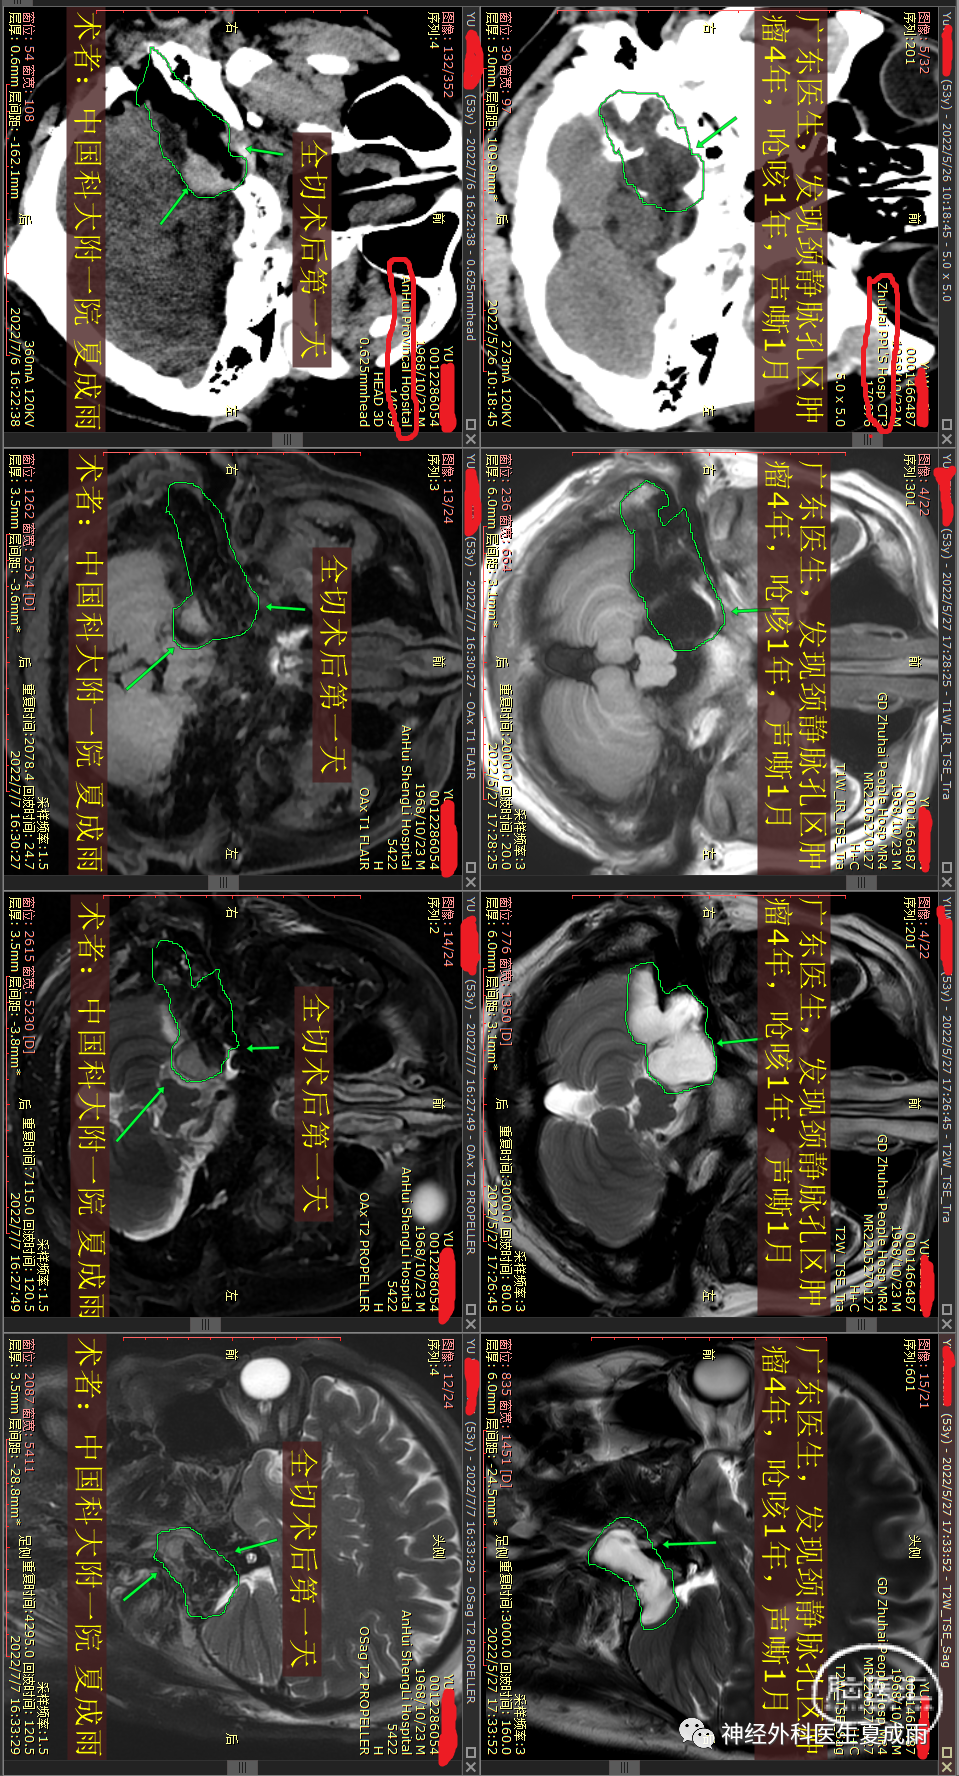

手术前后对比⏬

近2年逐渐出现声音嘶哑,吞咽困难,右肩疼痛,伸舌偏,在珠海及北京检查影像。

影像特点:肿瘤为颈静脉孔区颅内外沟通型占位,略有强化,周边及瘤内有钙化成分,肿瘤非钙化成分弥散略受限。

综合分析:该患者进展缓慢,结合其影像特点,考虑?决定行神经电生理监测下改良枕下远外侧入路颈静脉孔区肿瘤切除术。